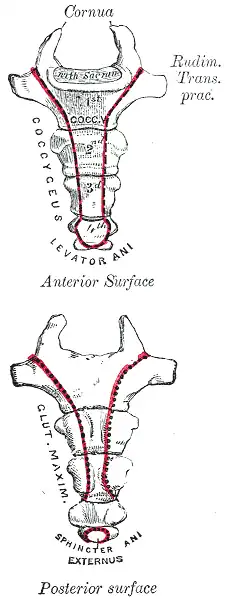

Description

Le coccyx est une pièce osseuse de forme triangulaire symétrique de base supérieure et à sommet inférieur. Il est aplati d'avant en arrière. Il est situé dans le prolongement du sacrum.

On lui décrit deux faces, une antérieure et une postérieure, deux bords externes, une base et un sommet.

Face antérieure

La face antérieure est légèrement concave et marquée de trois rainures transversales reliquat de la fusion des vertèbres coccygiennes.

Sur cette face s’insèrent le ligament sacro-coccygien antérieur et les muscle coccygien et élévateur de l'anus. Elle contribue au soutien du rectum.

Face postérieure

La face postérieure est convexe, marquée par des rainures transversales similaires à celles de la face antérieure. Latéralement se présentent une série de tubercules osseux reliquat des processus articulaires des vertèbres coccygiennes.

Bords latéraux

Les bords latéraux sont irréguliers et obliques en bas et en dedans. Dans leur partie supérieure des cornes latérales sont proéminentes, elles correspondent aux processus transverses de la première vertèbre coccygienne.

Les bords sont des zones d'insertion des ligaments sacro-tubéraux et des muscles coccygiens.

Base

La base s'articule avec la face articulaire du sommet du sacrum. Elle présente deux petites cornes correspondant aux apophyses articulaires supérieures de la première vertèbre coccygienne qui s'articule avec les cornes sacrales et complète de chaque côté le foramen qui transmet la division postérieure du cinquième nerf sacré .

Apex

Le sommet ou apex donne insertion au sphincter externe de l'anus.